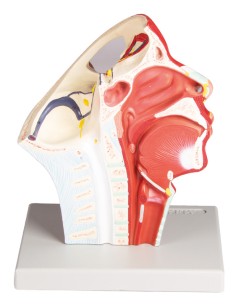

3B Scientific, modello anatomico funzionale di laringe: W42503